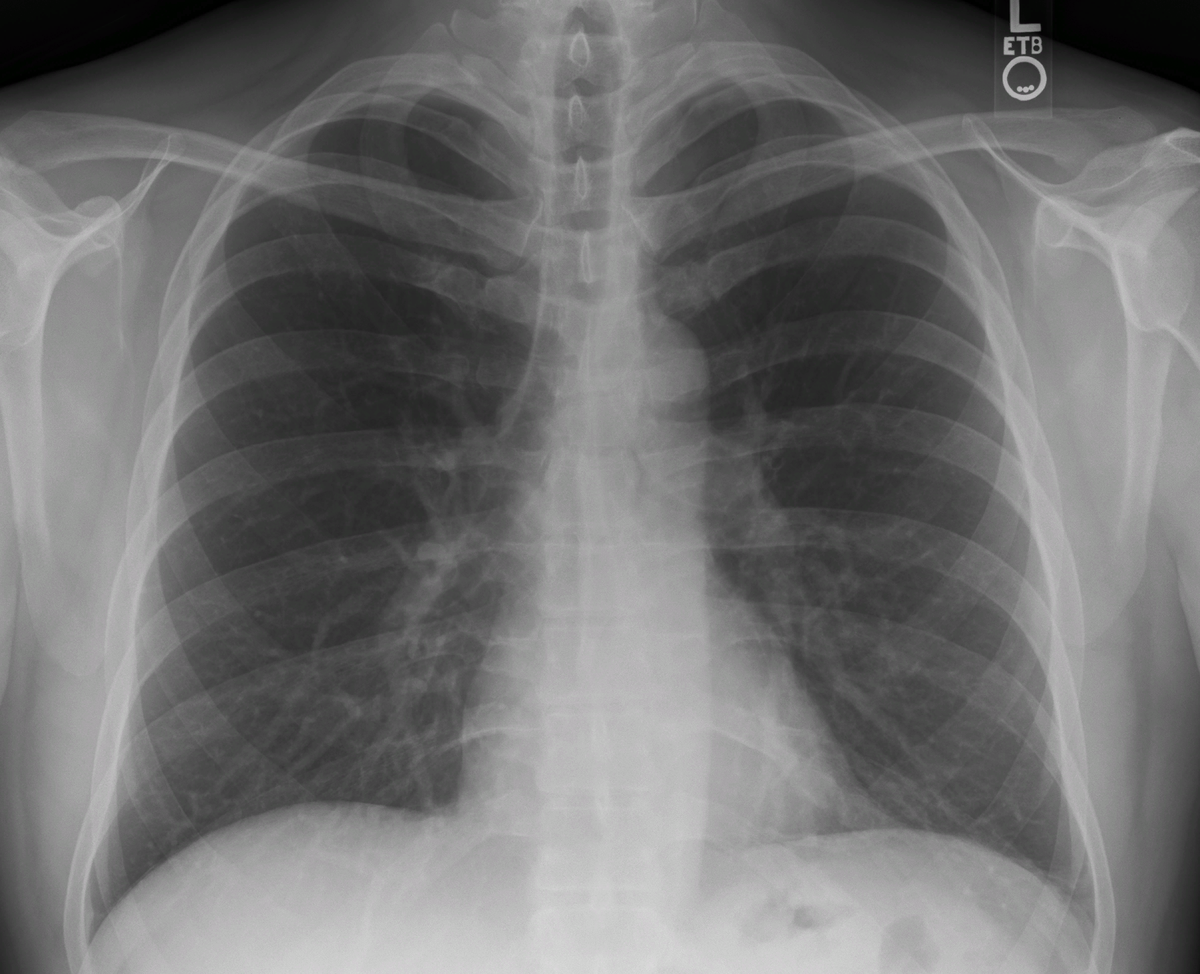

Чтобы вовремя подтвердить диагноз, необходимо выполнение рентгенологического исследования органов грудной клетки, где можно обнаружить воспалительную инфильтрацию. Именно этот метод диагностики становится ключевым в распознании пневмонии в этой группе пациентов